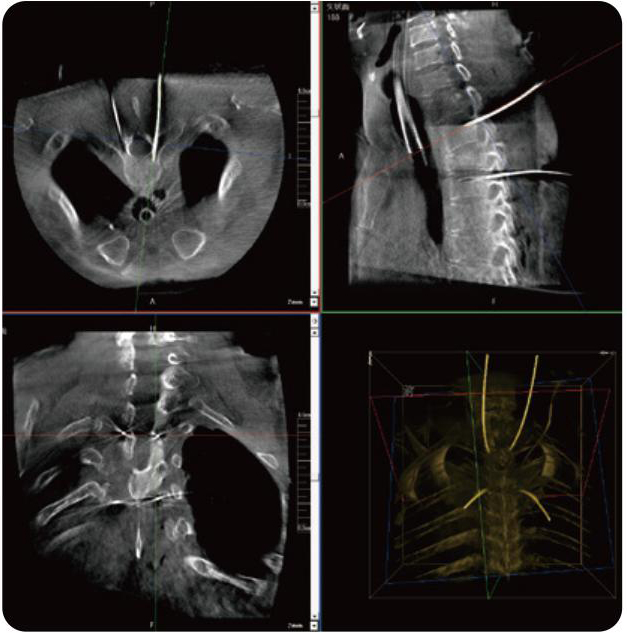

PL300B可應(yīng)用于多節(jié)段脊柱外科手術(shù),輔助醫(yī)生定位病灶部位,為脊柱外科手術(shù)(經(jīng)皮椎體成形術(shù)、椎弓根螺釘內(nèi)固定術(shù)等術(shù)式)提供術(shù)前手術(shù)流程規(guī)劃、入釘位置、角度可視化引導(dǎo),模擬仿真入釘輔助。

PL300B搭配普愛醫(yī)療自主研發(fā)生產(chǎn)的平板3D C形臂,借助一體化自適應(yīng)配準(zhǔn)( 軌跡配準(zhǔn))技術(shù),通過(guò)追蹤C(jī)形臂三維采集軌跡,自動(dòng)完成圖像坐標(biāo)建立和系統(tǒng)坐標(biāo)配準(zhǔn)。配準(zhǔn)精度更高,操作步驟少,系統(tǒng)運(yùn)作效率高。